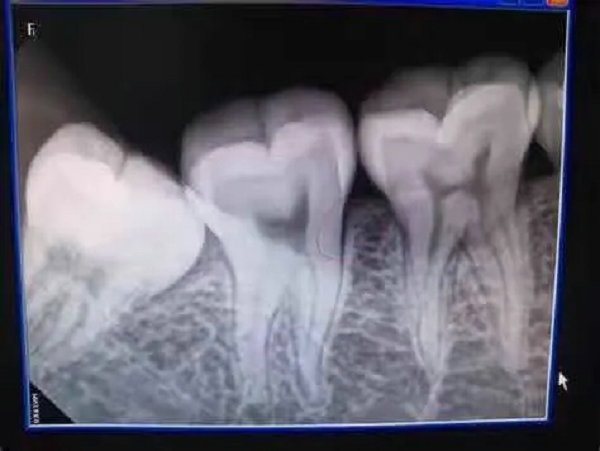

2.根尖片(小牙片):单拍1-2颗牙齿,主要用于深的牙洞、根管治疗及隐匿性的疾患的查明;